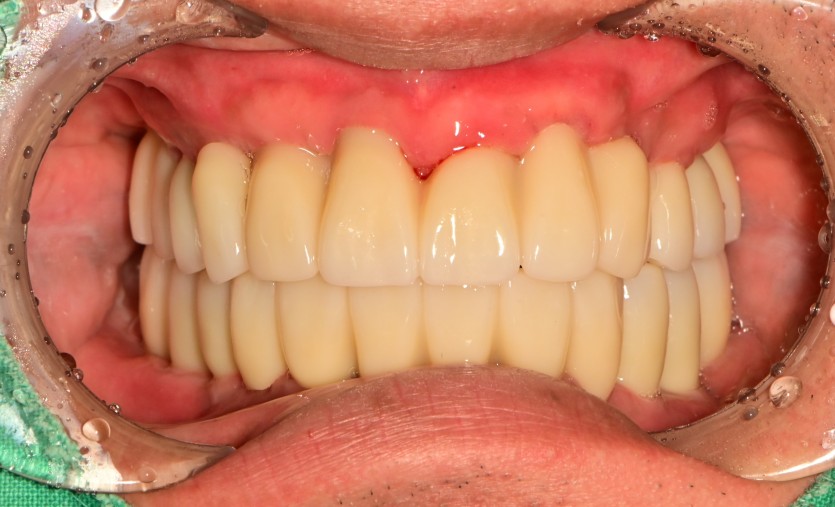

만 53세 전체 임플란트

전체 임플란트 증례입니다.

18개의 임플란트로 완성하였습니다.